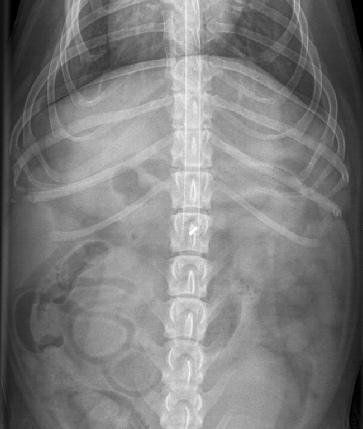

I metodi diagnostici utilizzati dai neurologi veterinari comprendono

esame fisico e racolta dell'anamnesi,

valutazione radiografica (in bianco nero e con mezzo di contrasto-MIELOGRAFIA)

analisi del liquido cerebrospinale,

risonanza magnetica e TC,

test elettrodiagnostico che comprende la valutazione della velocità della conduzione nervosa.

esame di potenziali evocati uditivi-BAER.

Epilessia e malattie neuromuscolari possono avere un impatto significativo sulla salute del vostro animale e devono essere affrontati immediatamente in quanto possono presto diventare ancora più dannosi senza un trattamento. I progressi nella tecnologia hanno aiutato neurologi nella localizzazione delle lesioni neurologiche con conseguente allungamento della vita degli animali.

Un esame diagnostico completo sarà fatto per stabilire come trattare correttamente un paziente con una malattia neurologica. La prima cosa che facciamo è di stabilire se i sintomi si riferiscono ad un problema all'interno del sistema nervoso. Se i disturbi sono neurologici, andiamo a localizzarli e valutare l'entità del problema. Una volta che questo è stato determinato discuteremo le diverse opzioni di trattamento.